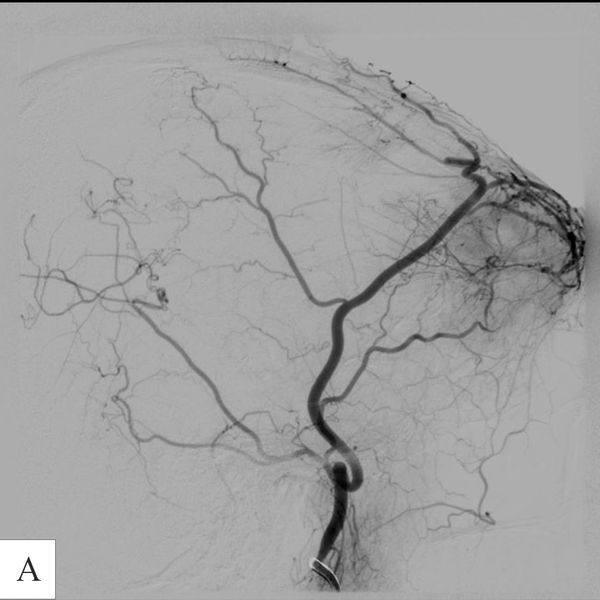

- КТ-ангиографии сосудов головного мозга: выраженная сосудистая сеть опухоли.

- Эмболизацию сосудистой сети опухоли (т. е. перекрытие кровоснабжения). Было принято решение ограничиться выключением из кровотока передне-латеральных отделов сосудистой сети, поскольку более радикальная эмболизация могла нарушить кровоснабжение в бассейне глазной артерии.